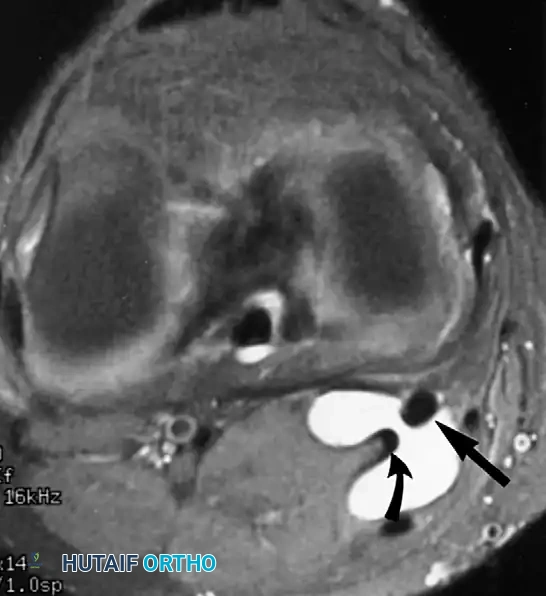

لا تقتصر قوة الرنين المغناطيسي على مفصل الورك فحسب، بل تمتد لتشمل المفاصل الأخرى كالركبة، مما يثبت فعالية هذه التقنية في كشف أدق التفاصيل التشريحية والمرضية في العظام والغضاريف. نستعرض هنا بعض الأمثلة التي توضح دقة الرنين المغناطيسي في تشخيص إصابات المفاصل:

هذه الصور تؤكد بما لا يدع مجالا للشك أن الاعتماد على الرنين المغناطيسي يوفر خريطة طريق واضحة للطبيب المعالج، سواء كان يتعامل مع كيس زلالي، أو كدمة عظمية، أو كسر خفي في صفيحة النمو، أو آفة غضروفية، مما ينعكس إيجابا على دقة التشخيص في مفصل الورك والمفاصل الأخرى.